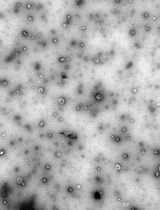

We previously used ginger-derived lipid nanoparticles (GDNPs) for orally delivering CD98 siRNA (Zhang et al., 2017) and 6-shogaol (Yang et al., 2021) to treat ulcerative colitis. These studies suggested that GDNPs could overcome the challenges of oral drug delivery. Further, we found that monogalactosyl-diacylglycerol (MGDG), digalactosyl-diacylglycerol (DGDG), and phosphatidic acid (PA) constitute more than 90% of the total lipids of GDNPs (Zhang et al., 2016; Zhang et al., 2017). In this protocol, we will describe how to use these three lipids at the same ratios found in the GDNPs in the synthesis of new lipid nanoparticles (nLNPs) to encapsulate IL-22 mRNA. The nLNP-encapsulated mRNA showed its therapeutic efficacy in one of our recently published studies (Sung et al., 2022).

Interleukin-22 (IL-22) has been demonstrated as a critical regulator of epithelial homeostasis and repair; it showed an anti-inflammatory effect against ulcerative colitis. Local microinjection of IL-22 cDNA vector has been shown to be effective in treating ulcerative colitis in mouse models. However, microinjection comes with multiple technical challenges for routine colon-targeted drug delivery. In contrast, oral administration can get around these challenges and provide comparable efficacy. We showed in previous studies that oral administration of new lipid nanoparticles (nLNP)-encapsulated IL-22 mRNA targets the colon region and efficiently ameliorates colitis. This protocol describes the details of preparing and characterizing the nLNP-encapsulated IL-22 mRNA using three major lipids that mimic the natural ginger-derived nanoparticles. It provides an nLNP platform that can be used to orally deliver other types of nucleic acids to the colon.